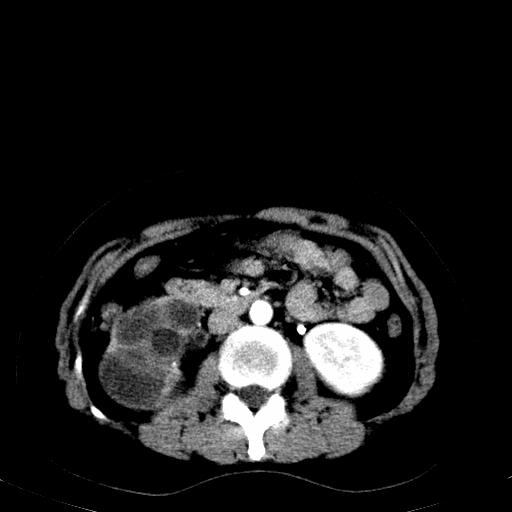

右肾重度积水,以肾盏积水明显,有分隔,上段输尿管轻度扩张,管壁增厚,考虑肾结核可能,请结合尿检查,胸部拍片排除肺结核。

右肾重度积水,建议ct向下扫描或逆行造影,左肾及左输尿管结石 .

第一个序列应该是延迟图像吧;

结合强化图片看ivp意义不大,建议作逆行造影看一下;

左肾不是结石,是造影后改变.右肾积水,功能仅存.